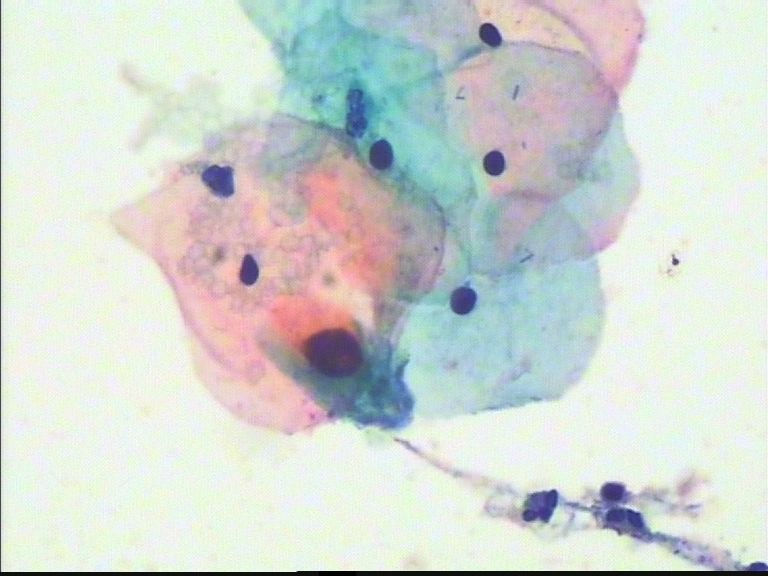

无论CIN2,3,原位癌,在细胞学上都应有其证据.如果没有,不能想当然猜测,虽然报的结果可能与实际不符,但原因也许不是单一的.在力求达到"真实"的同时,也要规避风险.作为筛查方法,够了.

本例的细胞看不出CIN3,LSIL是可以的,也许有倾向于CIN2的可能,但不能直接诊断HSIL.原因找不到确切的,因为原因不是单一的.比如取材\病变局限\制片.................